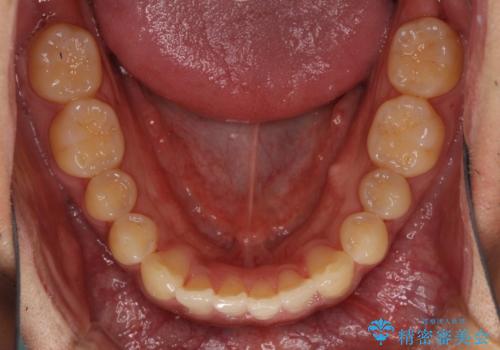

- 前歯のデコボコを気にして来院された患者様です。

主に下顎歯列全体の後方移動とIPR(歯と歯の間を削る)によってデコボコが解消するように設計し、インビザラインにより治療を行うこととしました。

インビザライン矯正特有の、治療後半で前歯のみが強く接触する症状が発現し、咬み合わせ改善に期間を要することとなりました。